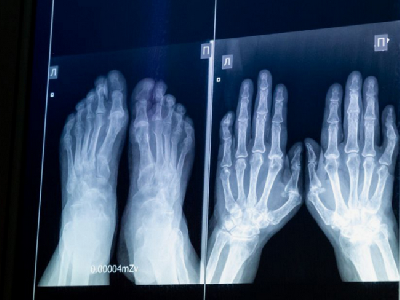

Детская городская клиническая больница №8 в областном центре обзавелась новейшим цифровым рентген-аппаратом. Оборудование поступило в рамках национального проекта «Семья» программа «Охрана материнства и детства»Новая техника позволяет получать высокодетализированные снимки благодаря цифровым технологиям. Это повышает точность диагностики и помогает врачам назначать более эффективное лечение.

Как рассказала заведующая отделением лучевой диагностики поликлиники № 1 ДГКБ № 8 Жанна Зеленина, аппарат прост в использовании и дает хорошее качество изображения. Важно и то, что результаты исследований автоматически загружаются в медицинскую систему «Комета»: это обеспечивает преемственность между разными медучреждениями и специалистами.